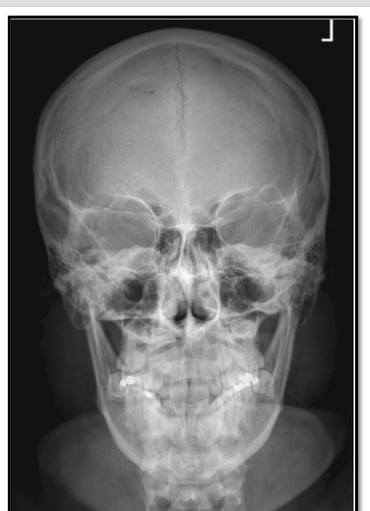

Q

what is the issue here

A

way too much angle

what is the correction

20-25 deg more caudad

lift chin to change OML by 20-25 deg